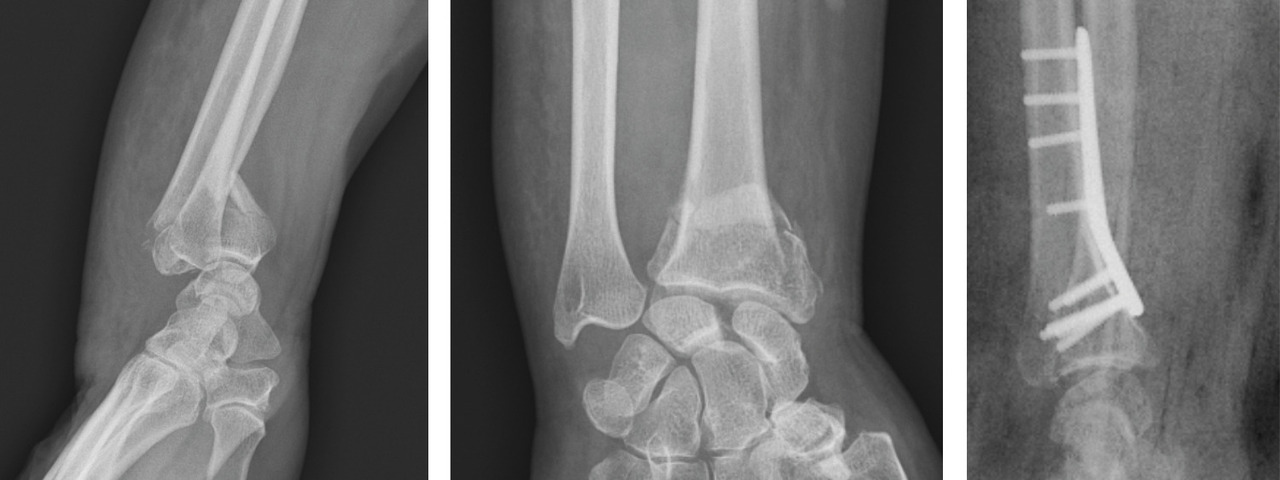

Au niveau métaphysaire le déplacement peut être postérieur ou antérieur (fig. 6). En ce qui concerne le déplacement postérieur, il est important de se souvenir que la surface articulaire regarde vers l’avant. En d’autres termes, dès que cela n’est plus le cas, même si la surface articulaire n’est pas orientée vers l’arrière, il s’agit d’un déplacement postérieur. Classiquement, le déplacement postérieur est lié à un mécanisme dit en compression-­extension, c’est-à-dire une chute sur la main, le poignet étant en extension (fig. 7). Le déplacement est dit antérieur s’il y a une exagération de l’orientation antérieure de l’épiphyse radiale. Ce déplacement est classiquement lié à un mécanisme dit en compression-flexion, c’est-à-dire une chute sur la main, le poignet étant en flexion (fig. 7). La plupart du temps, ce déplacement postérieur ou antérieur s’accompagne également d’un déplacement externe, avec un tassement au niveau de la corticale latérale (fig. 8). Outre le déplacement antérieur, postérieur ou latéral, il est très important d’analyser au niveau du foyer de fracture métaphysaire l’importance de la comminution qui peut être uniquement postérieure, ou antérieure, ou circonférentielle, ce qui conditionne la stabilité de la fracture et oriente vers le type d’ostéosynthèse à réaliser.

L’analyse de l’épiphyse va permettre de déterminer si la fracture est articulaire ou extra-articulaire. Dans la très grande majorité des cas, la fracture est articulaire. Il existe très fréquemment un fragment postéromédial qu’il est important de rechercher car il faudra le stabiliser lors du traitement. Mais la fracture articulaire peut être plus complexe, en T ou en croix (fig. 9). Enfin, il peut exister des enfoncements de fragments ostéochondraux à l’intérieur du spongieux épiphysaire (appelé par les Anglo-Saxons « die punch »). Sur les fragments épiphysaires s’attachent les ligaments radiocarpiens. Ainsi, une traction dans l’axe permet, par le biais de ses ligaments (effet de ligamentotaxis), de réduire au moins partiellement la fracture. En revanche, les fragments ostéochondraux qui sont enfoncés dans le spongieux n’ont pas d’attaches ligamentaires et ne se réduisent pas par les manœuvres de traction. Il peut arriver que les fractures soient uniquement épiphysaires. C’est le cas des fractures dites marginale antérieure, marginale postérieure et cunéenne externe. Cette dernière est importante à connaître et à dépister car elle s’accompagne relativement fréquemment de lésion ligamentaire intracarpienne, notamment scapholunaire.

Enfin, il est important d’analyser le versant ulnaire pour savoir si la fracture de l’extrémité inférieure du radius est isolée ou bien associée à une fracture de l’extrémité distale de l’ulna ou encore à une fracture de la styloïde ulnaire. Cette fracture est l’équivalent d’un arrachement du ligament triangulaire du carpe et peut être source d’instabilité radio-ulnaire distale (fig. 10). Il faut également analyser le rapport entre l’épiphyse radiale et l’épiphyse ulnaire, à la recherche d’une inversion de l’index radio-ulnaire témoin d’une ascension de l’épiphyse radiale.